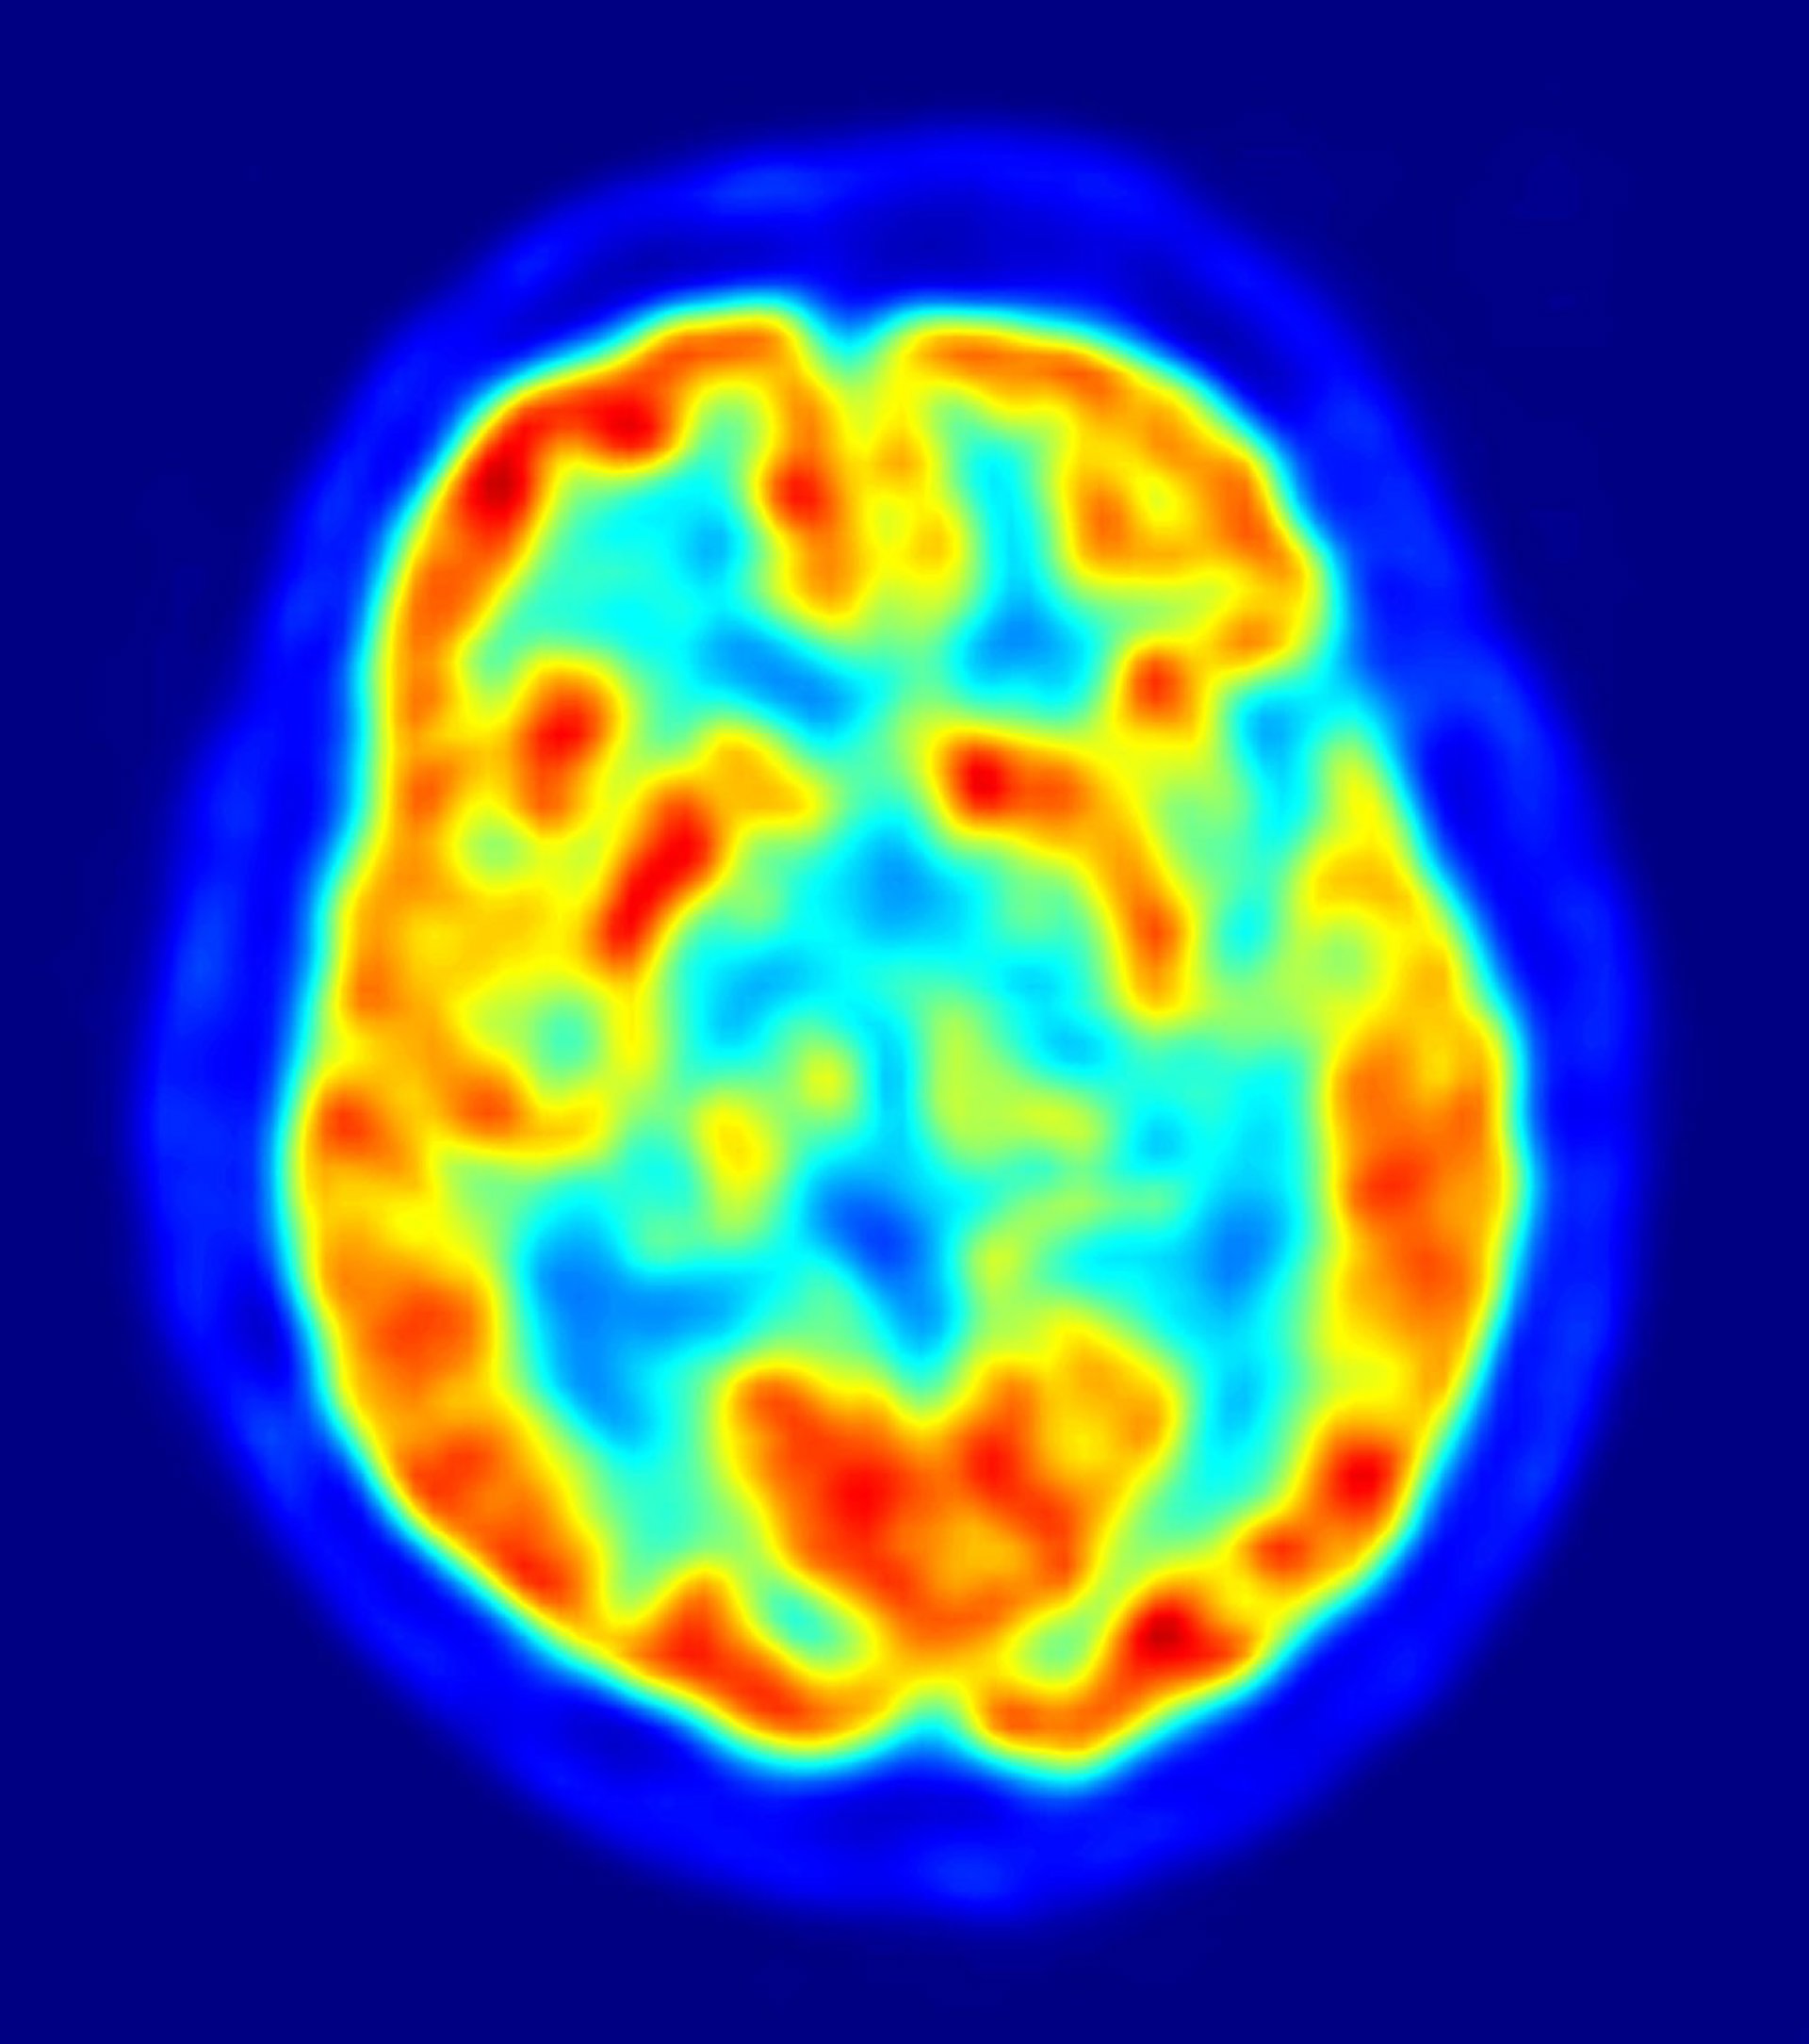

Sin embargo, en un estudio realizado en 2010, el equipo de investigadores del laboratorio de Long, descubrió que los genes más recientes podrían ser tan importantes como los más antiguos. En el nuevo estudio, el doctor Yong Zhang, y sus colaboradores, fusionaron una base de datos sobre la edad de los genes con transcripciones de datos de seres humanos y ratones, para buscar cuándo y dónde se expresan los genes específicos de cada especie. Los investigadores encontraron un mayor porcentaje de expresión de genes jóvenes en primates que en el cerebro de los ratones. Los genes jóvenes específicos de los humanos también se observaron en el cerebro fetal, cuando el órgano está aún en desarrollo, y en estructuras cerebrales únicas en primates, como la neocorteza y la corteza prefrontal.